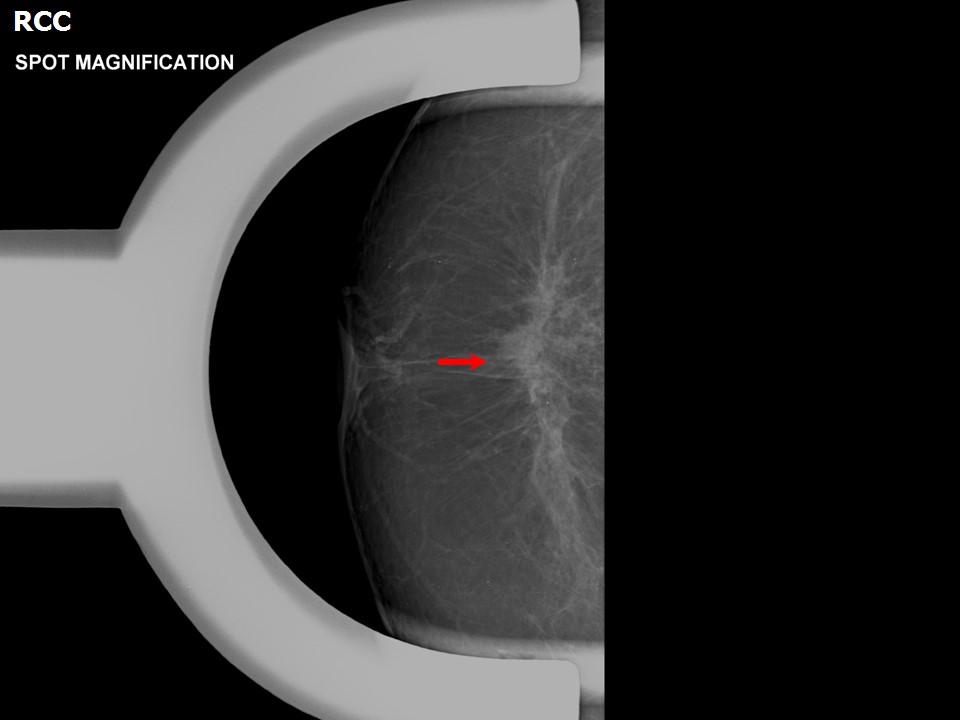

Atlas of breast cancer early detection

From screening.iarc.fr

Atlas of breast cancer early detection Rfid Lumpectomy The specimen radiograph (f) of the lumpectomy tissue showing the scout device and biopsy clip within the specimen. The radiofrequency identification (rfid) technique is a wireless localization technique used for intraoperative breast lesion. This technology is called radiofrequency identification, or rfid tagging and in the world of breast surgery, we call it rfid tag localization. This is a safe and. Rfid Lumpectomy.